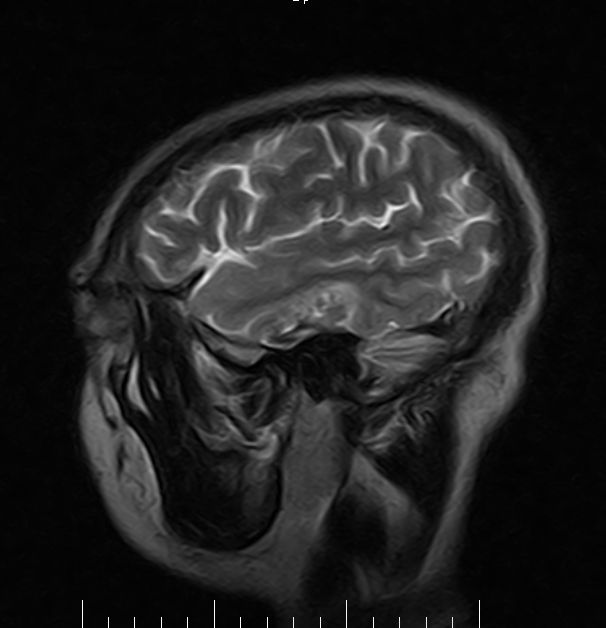

标题: MRI2379:30岁,男,癫痫10年,请各位看一下;CT示:左颞叶钙 [打印本页]

标题: MRI2379:30岁,男,癫痫10年,请各位看一下;CT示:左颞叶钙

左颞叶区见不规则点状混杂信号影

考虑血管畸形

支持2楼 左颞叶区见不规则点状混杂信号影,考虑动静脉畸形。

考虑左侧颞叶脑血管畸形(avm)。

考虑左侧颞叶脑血管畸形(avm)。----t1低等高混杂信号,t2等高信号周边较多流空血管影[冠状位明显],mra左侧大脑中动脉受压,远侧聚集.